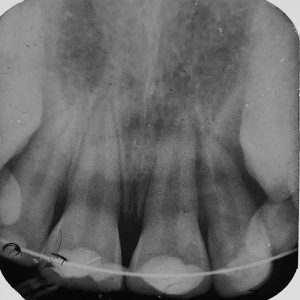

- Case report titled “ Management of traumatic anterior tooth with vital pulp using MTA pulpotomy in 10year old child –A case report has been published in journal of Indian Dental Association 2024